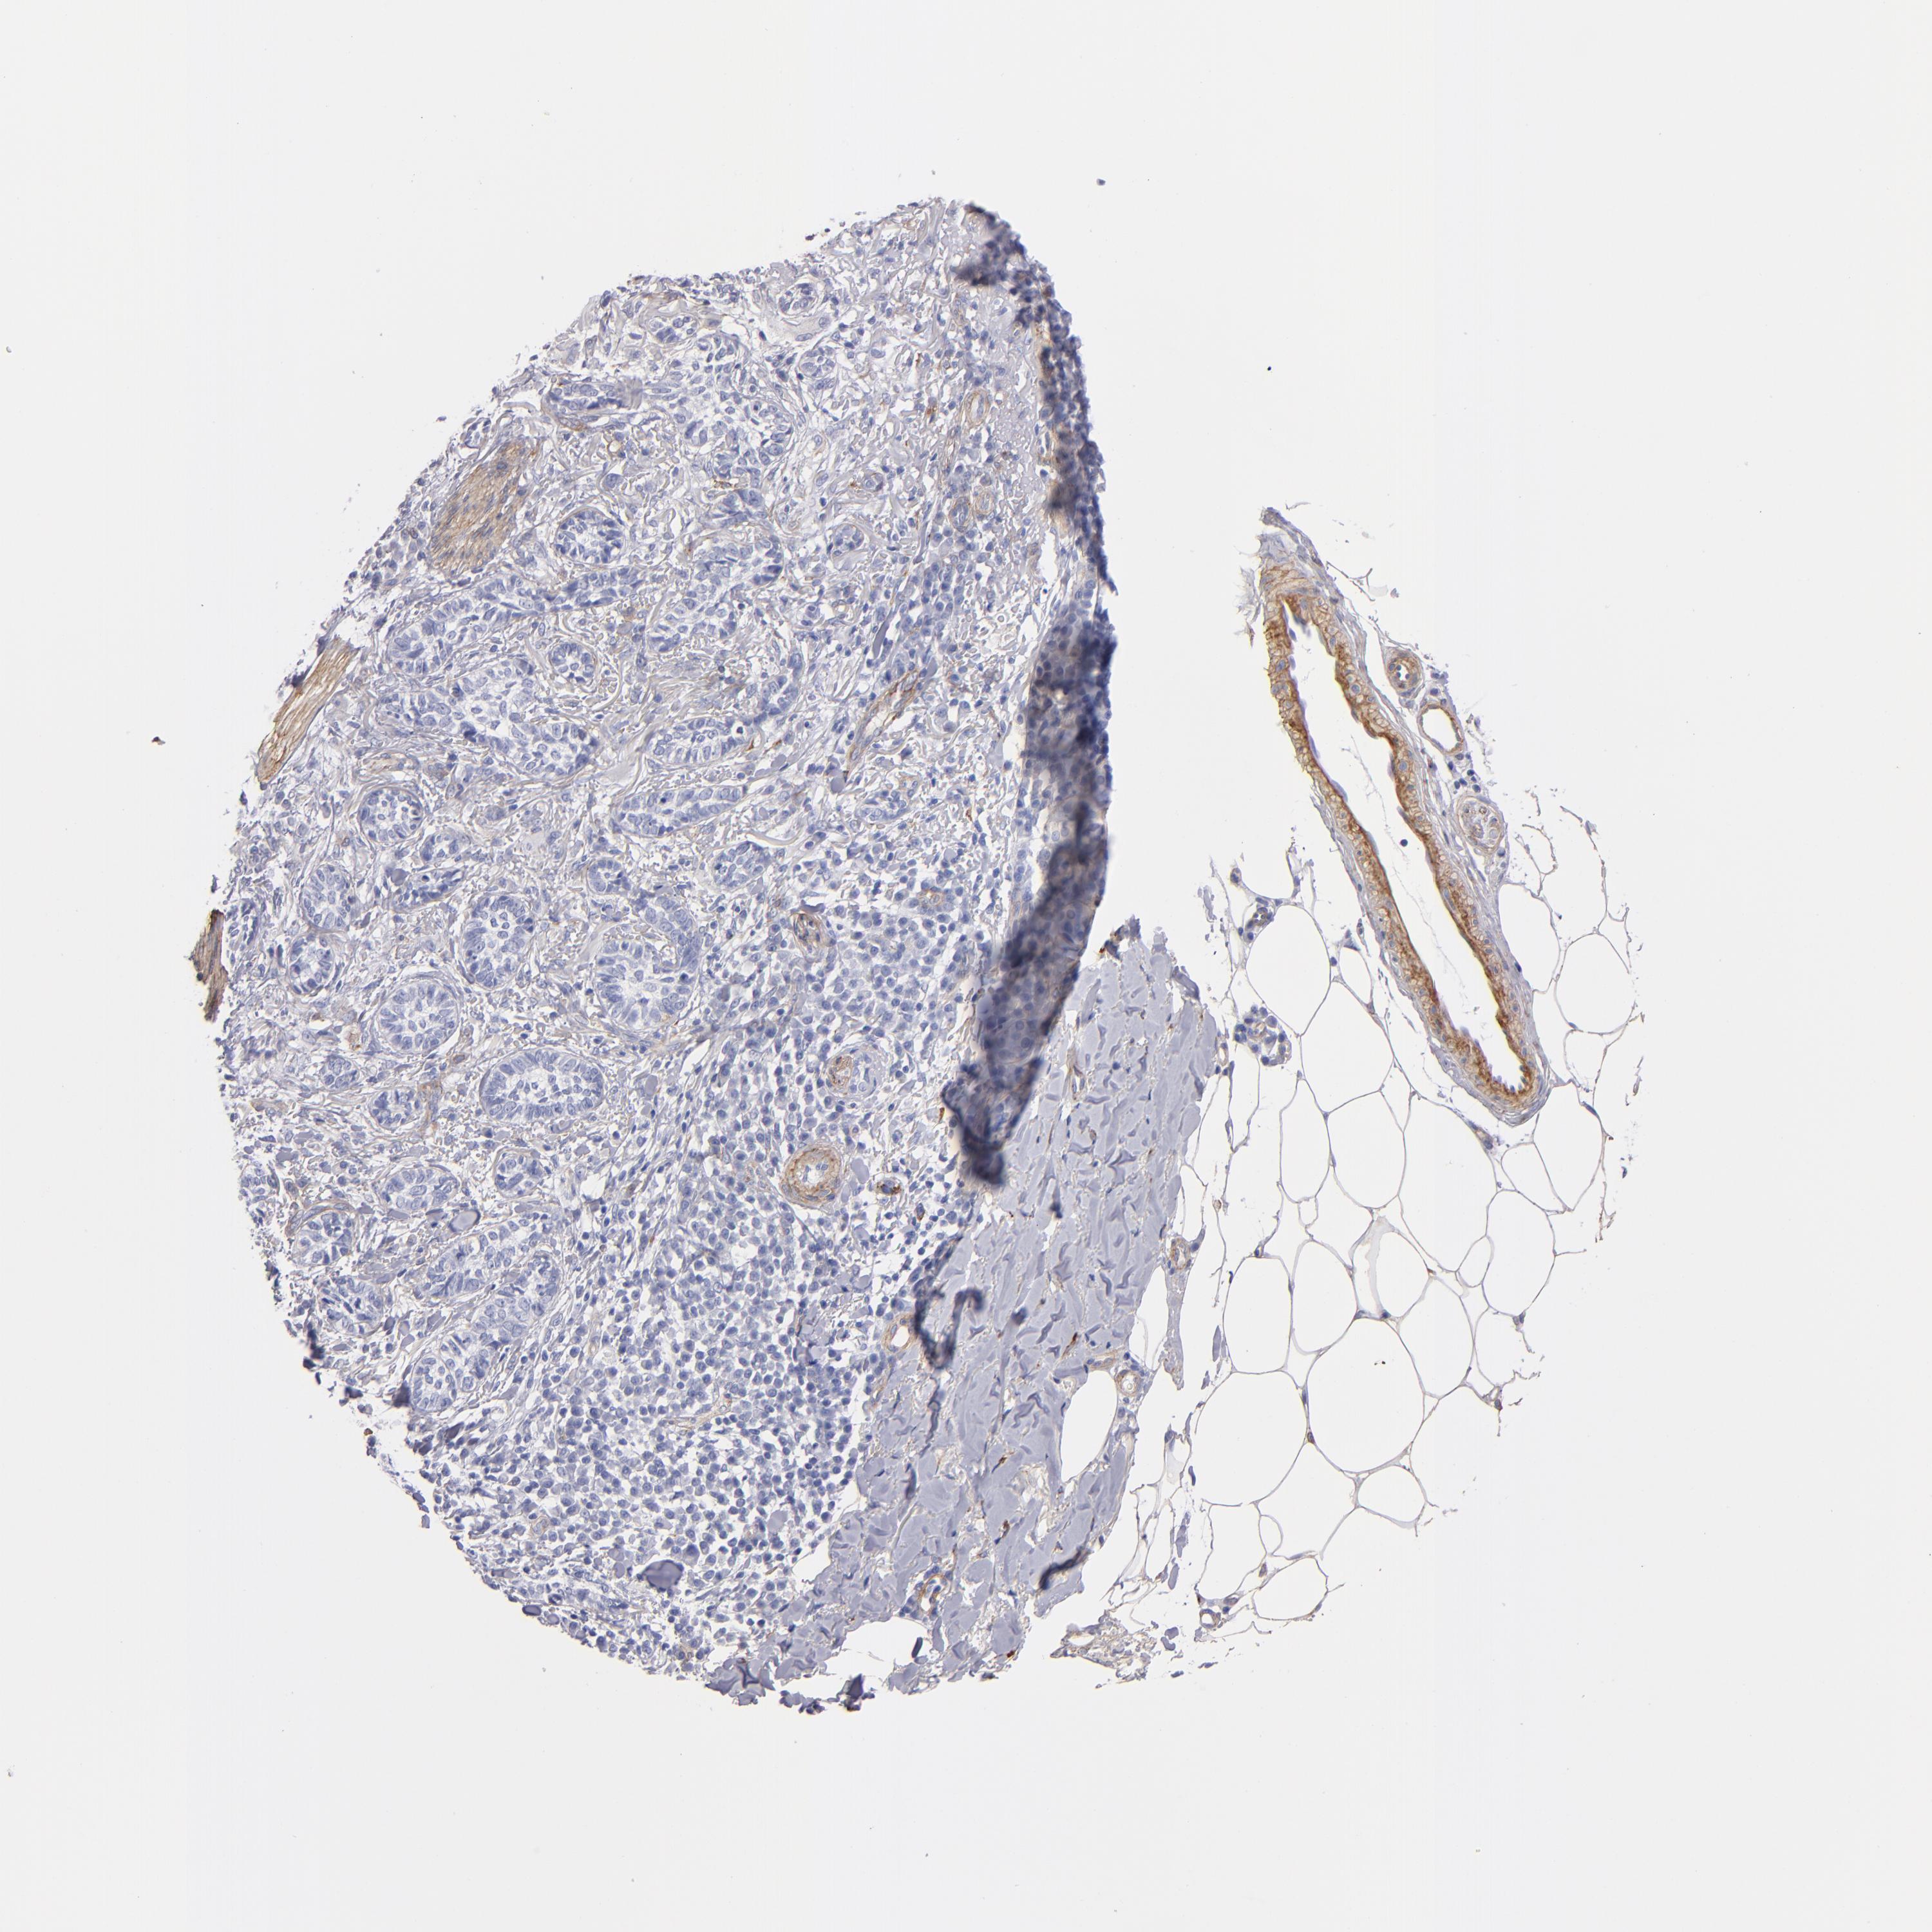

Basal cell and squamous cell cancer

SKIN CANCER - Protein expressioni

A mouse-over function shows sample information and annotation data. Click on an image to view it in a full screen mode. Samples can be filtered based on level of antibody staining by selecting one or several of the following categories: high, medium, low and not detected. The assay and annotation is described here.

Antibody stainingi

Antibody staining in the annotated cell types in the current human tissue is reported as not detected, low, medium, or high, based on conventional immunohistochemistry profiling in selected tissues. This score is based on the combination of the staining intensity and fraction of stained cells.

Each image is clickable and will lead to virtual microscopy that enables deeper exploration of all samples and also displays staining intensity scores, fraction scores and subcellular localization as well as patient and tissue information for each sample.

Antibody HPA001908

Antibody HPA001909

Antibody CAB004486

Antibody CAB078163

Squamous cell carcinoma, NOS

Basal cell carcinoma